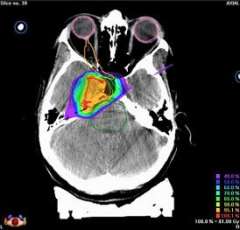

Conformal radiation dose delivery with Novalis. This CT image shows the how this pear-shaped tumor, outlined with a thin red line, can be evenly dosed with the appropriate amount of radiation (in the 90th percentile of the prescribed dose, or the yellow area) in a manner that matches the shape of the tumor. A similar treatment plan would not be possible with Gamma Knife.